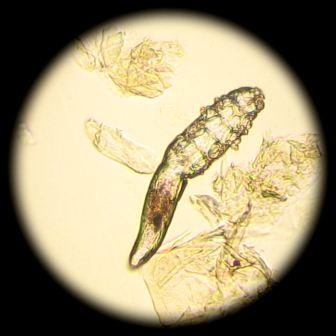

Заболевание кожи и придатков, возбудитель клещ-железница (демодекс).  Демодекс — условно-патогенный паразит; обитает в волосяных фолликулах, мейбомиевых железах век, сальных железах кожи человека и некоторых животных.

Очаги поражения локализуются обычно на коже лица, особенно вокруг рта, глаз, на носу, веках. Характерны эритема, шелушение, островоспалительные красные папулопустулы, везикулопустулы, а также блефарит. Заболевание напоминает красные угри, периоральный дерматит, начальные проявления красной волчанки.  Течение хроническое, обострения наступают преимущественно в весенне-летний период. Диагноз устанавливают на основании клинической картины и обнаружения клеща в содержимом пустул, секрете сальных желез, в соскобе и чешуйках из очагов поражения. Для определения возбудителя инфицированный материал, обработанный в капле изотонического раствора хлорида натрия или 10—20% раствора едкой щелочи, исследуют под малым увеличением светового микроскопа. Дифференциальный диагноз проводят с красными угрями, вульгарными угрями, периоральным дерматитом, красной волчанкой.